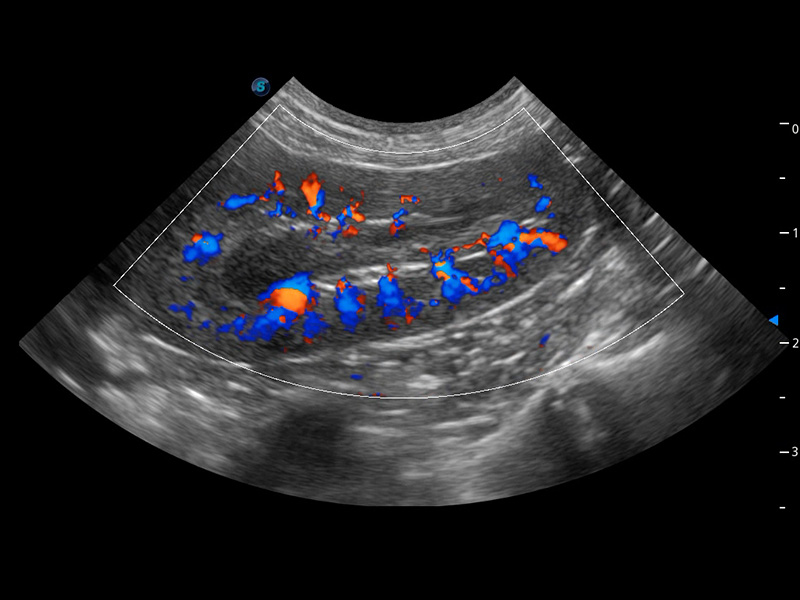

Micro F 显微血流成像

通过创新的Matrix E自适应滤波器和超长时间域算法,极大提升超低速微细血流的检出能力,同时更精准地滤除软组织和噪声信号,为兽用医生提供以往无法通过常规血流获得的疾病诊断信息。

Bright Flow 立体血流成像

在传统二维血流成像的基础上,呈现血流的立体感,具有动感的生命力之美。精确区分不同血管的空间关系,提高了血流的视觉敏感性。

优异的基础图像

(犬)肾脏血流